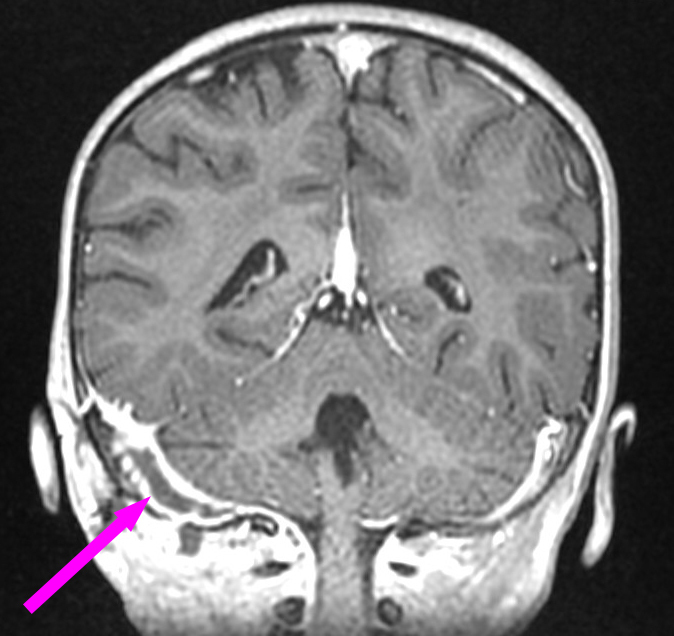

Voici l’imagerie que vous avez demandée. Devant le tableau, le radiologue a également choisi de faire une IRM.

Question 13 : Qu’en pensez-vous ?

Faux, la substance grise est grise, et la substance blanche est blanche (moyen mnémotechnique), c’est donc une séquence T1 (en T2, la substance grise apparaît en hypersignal). C’est ici un T1 avec injection de gadolinium

C’est une séquence T1 avec les vaisseaux en hypersignal franc. C’est donc un T1 avec injection de gadolinium

On peut voir sur le scanner une image très hypodense dans le sinus à droite (alors que le sinus gauche est normalement hyperdense). C’est très visible sur la coupe en IRM avec un caillot hypo-intense au milieu du sinus veineux à droite

Comme expliqué à la question précédente, l’intérêt est de chercher les complications intracrâniennes. Il n’y a pas ici d’abcès intracrânien, mais on retrouve une thrombophlébite importante du sinus sigmoïde droit. Insérer image « Figure10.jpg ». Insérer image « Figure11.jpg ». Insérer image « Figure12.jpg »